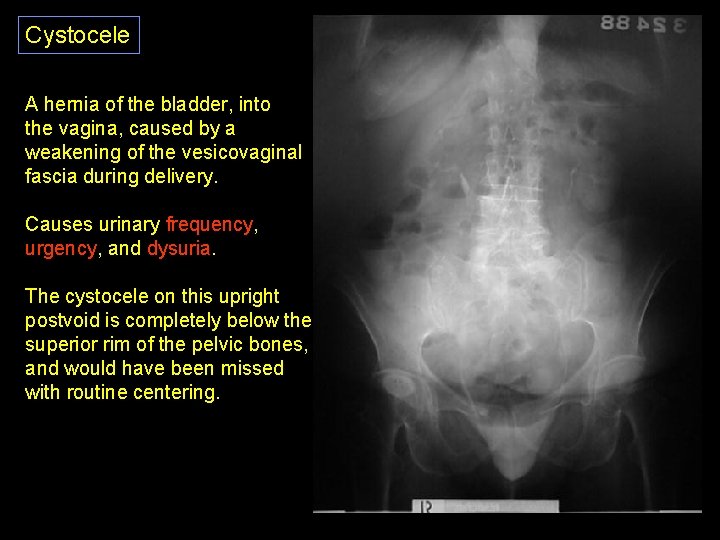

Cystocele A hernia of the bladder, into the vagina, caused by a weakening of the vesicovaginal fascia during delivery. Causes urinary frequency, urgency, and dysuria. The cystocele on this upright postvoid is completely below the superior rim of the pelvic bones, and would have been missed with routine centering.